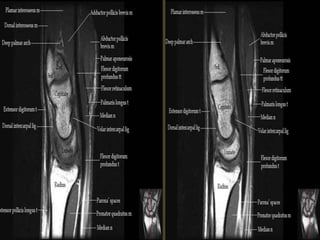

Wrist X-ray Anatomy.

The transverse carpal ligament (short arrows) extends from the hook of the hamate (long

arrow) to the tubercle of the trapezium (arrowhead), forming the floor of the carpal tunnel.

At the radial aspect of the carpal tunnel, the flexor digitorum tendons are arranged in two

rows (separated by dotted line), the profundus tendons deep to the superficialis tendons. The

flexor pollicis longus tendon (star) is positioned at the ulnar aspect of the tunnel, separated

from the flexor carpi radialis tendon (curved arrow) by a ligamentous reflection of the

transverse carpal ligament. The median nerve is indicated (asterisk). - See more at:

http://radsource.us/palmar-bursae-and-flexor-tendon-sheaths/#sthash.mSFX1u0c.dpuf